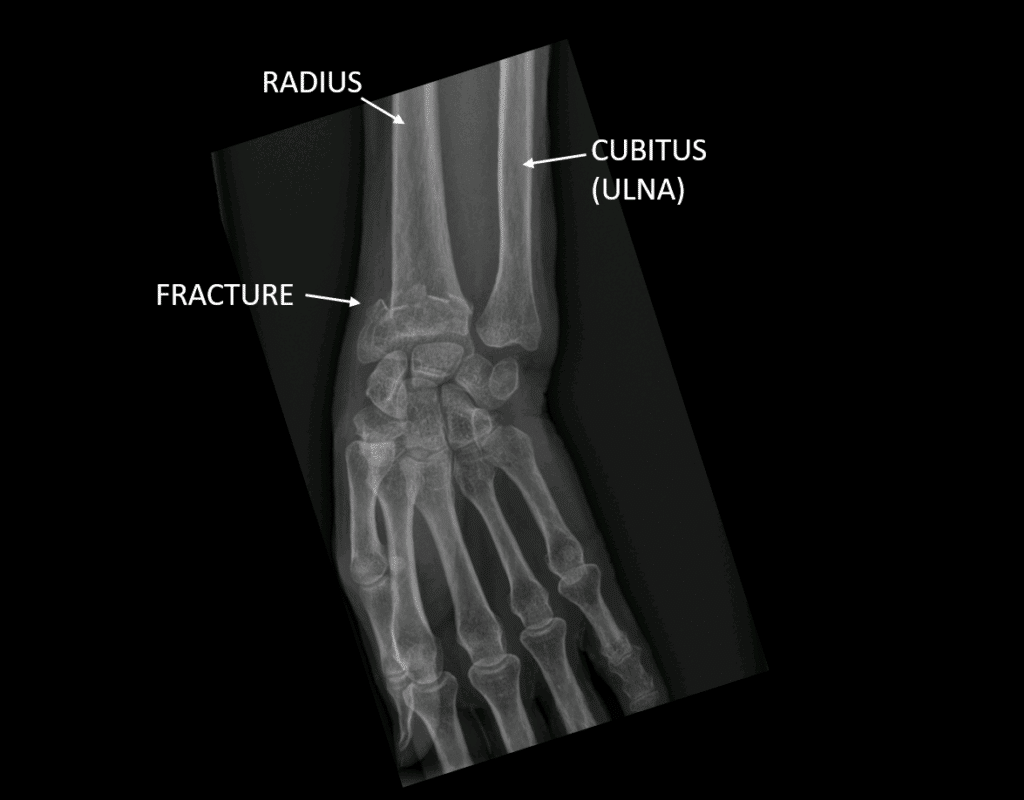

Fracture du (radius et cubitus) conseils kiné et auto Sport Apres Fracture Du Radius Other sport may be earlier but you. There continues to be discrepancies in. optimizing recovery after a distal radius fracture is a major concern. when can i return to sport? Distal radius fractures can be reset either with surgery (open reduction) or without it. if you play a sport, you can practice sports specific activities; Il convient. Sport Apres Fracture Du Radius.